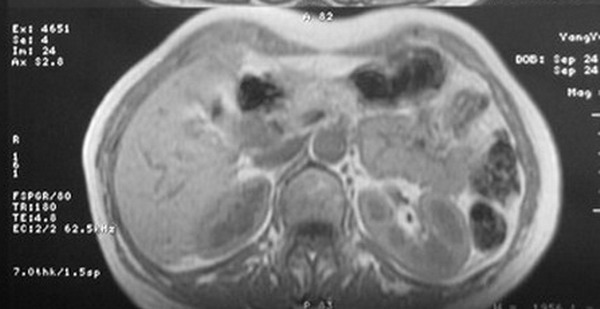

标题: MRI2066:腹膜后占位,请会诊,CT18531近期扫描图像

无明显不适,体检发现,

mri基本排除血管类肿瘤,明显强化说明极富血供,临床无症状,考虑胰岛细胞瘤可能大。

强化明显,并见有血管与之相连;考虑巨淋巴增生症.

极富血供的占位性病变,首先考虑良性,期待结果。